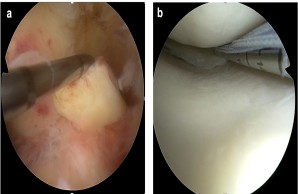

Fig.: Internal knee trauma as a typical example of common musculoskeletal injuries. (a) Fresh tear of the anterior cruciate ligament (ACL). Here, the ACL is pulled forward with a hook probe during arthroscopic exploration. (b) Arthroscopic suture of a torn meniscus in the posteromedial joint corner.